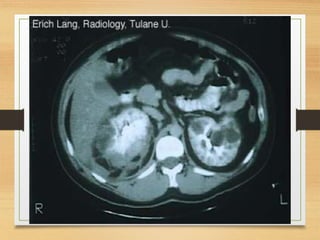

CASE 4

• A 64-year-old man presents with a 2-month history

of painless visible haematuria, hypertension, weight